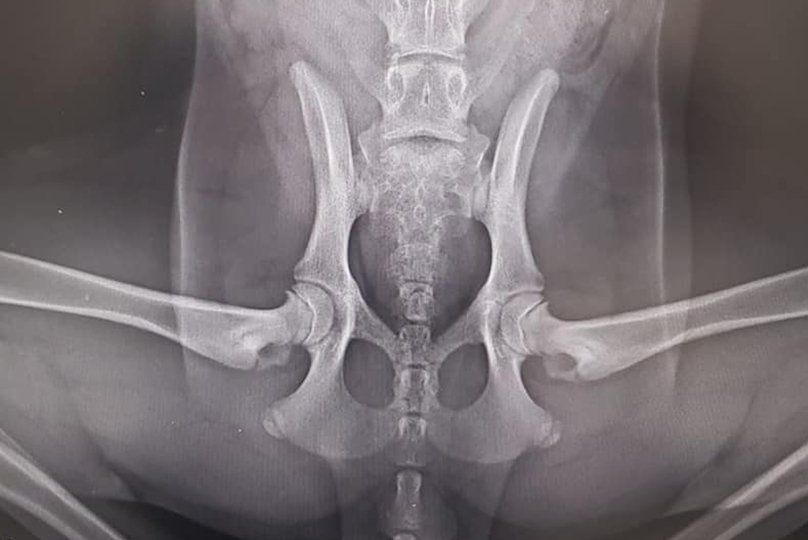

Displasia

La displasia di anca e la displasia di gomito sono patologie degenerative a carico di queste articolazioni. Sono ereditarie e interessano tutte le razze di cani di taglia media, grande e gigante (in particolare razze come il pastore tedesco, labrador, golden retriever, rottweiller, bovaro del bernese, san bernardo). Possono interessare anche i meticci che da adulti avranno un peso

superiore a 20 kg. Per diagnosticare in tempo utile queste patologie è necessaria prima visita ortopedica intorno ai 4 mesi di età e quindi uno studio radiografico completo in sedazione. La sedazione è indispensabile per la precisione del posizionamento e per eseguire test diagnostici specifici.